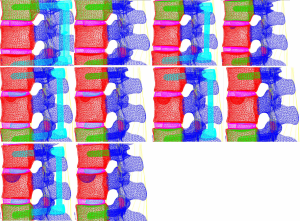

Models containing the implanted screw-rod system with five different defect sizes as well as five models with the screw-rod system removed were derived (defect diameters of 1/5, 2/5, 3/5, 4/5, and 5/5 of the anterior-two-thirds edge of the vertebral body, respectively) (Figure 12).